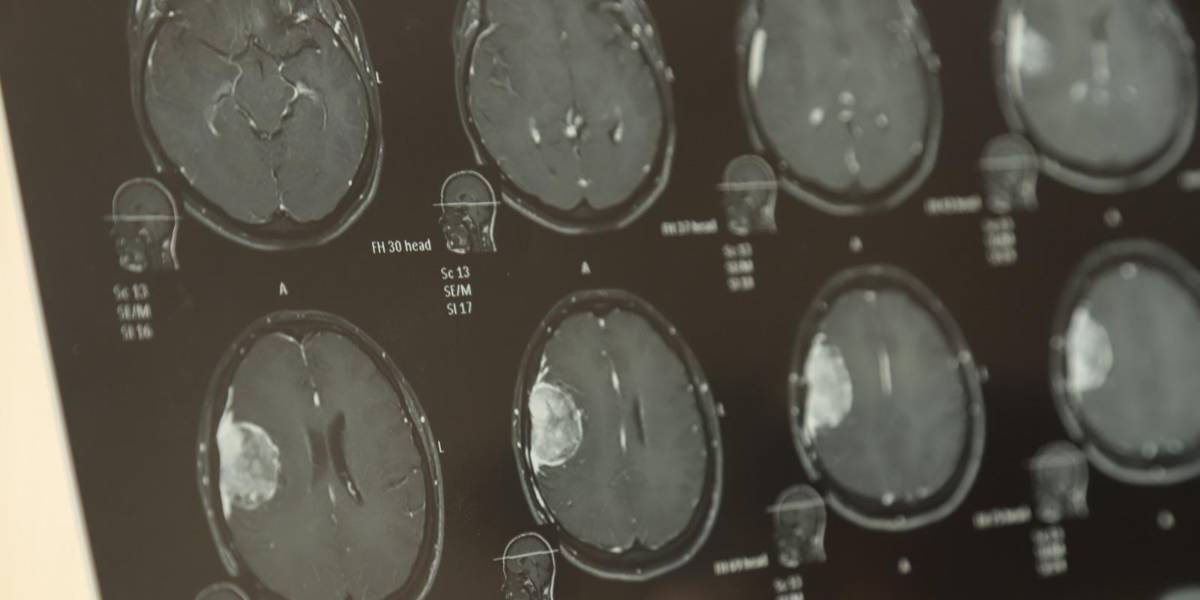

De 36 años, mamá de dos hijas, de 9 y 2 años y medio, Iris Analí narró cómo apenas 18 días antes se enteró de que en su cerebro está alojado un angioma al parecer benigno, que mide 4.3 centímetros por 3 centímetros.

“Con un neurólogo él me mandó hacer una resonancia y arrojó que era un tumor aparentemente benigno, pero ocupo una operación y sí es muy costosa. Me sale en 250 mil pesos”, comentó.

Clamó la ayuda de la ciudadanía con poquito o mucho para poder reunir la cantidad necesaria para ser operada; la cirugía es delicada por la zona donde se encuentra ubicado el tumor que envuelve una vena pegada al hueso y que tendrán que limar para colocar una placa.